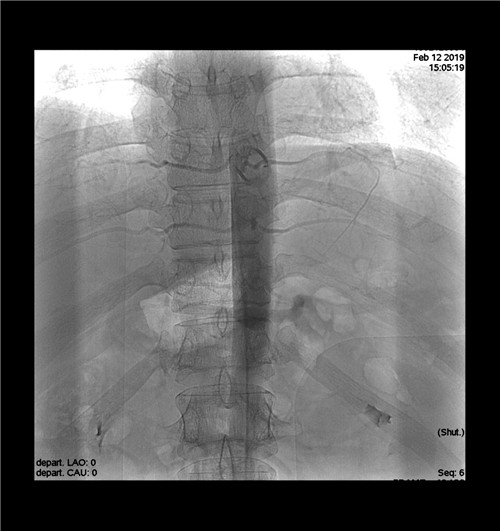

術(shù)后造影查看無(wú)血管并發(fā)癥

據(jù)介紹,血管內(nèi)去交感神經(jīng)術(shù)治療糖尿病,這種介入微創(chuàng)手術(shù)在局麻狀態(tài)下進(jìn)行,細(xì)長(zhǎng)導(dǎo)絲從股動(dòng)脈進(jìn)入,在血管造影下精準(zhǔn)定位,運(yùn)用帶六位電極的螺旋環(huán)通過(guò)射頻消融,毀損腹腔動(dòng)脈周?chē)慕桓猩窠?jīng),讓活躍的交感神經(jīng)進(jìn)入“休眠期”,從而起到降低血糖的效果。根據(jù)目前的研究,糖尿病患病史少于10年、年齡在18到75歲之間罹患頑固型2型糖尿病、合并代謝綜合征、多種藥物控制不佳的糖尿病患者,可以嘗試這種介入微創(chuàng)方法治療。